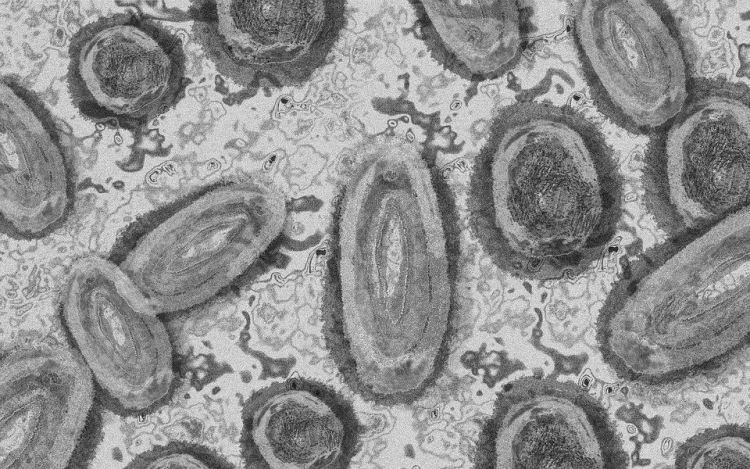

Tovább nőtt a majomhimlő-fertőzöttek száma Magyarországon

Újabb két embernél igazolt majomhimlő-fertőzést a Nemzeti Népegészségügyi Központ (NNK) a 33. héten - augusztus 15-től 21-ig -, ezzel 64-re nőtt a magyarországi esetek száma.

Az NNK korábban azt közölte, hogy a betegség általános, nem specifikus tünetekkel - lázzal, hidegrázással, izomfájdalommal, hátfájdalommal, fejfájással, fáradtsággal -, illetve a nyirokcsomók duzzanatával kezdődik, majd 1-3 nappal a bevezető tünetek után bőrkiütések jelennek meg. A kiütések sok esetben először az arcon, majd a tenyéren és a talpon fordulnak elő, de megjelenhetnek a szájnyálkahártyán, a nemi szerveken és a végbél környékén is.